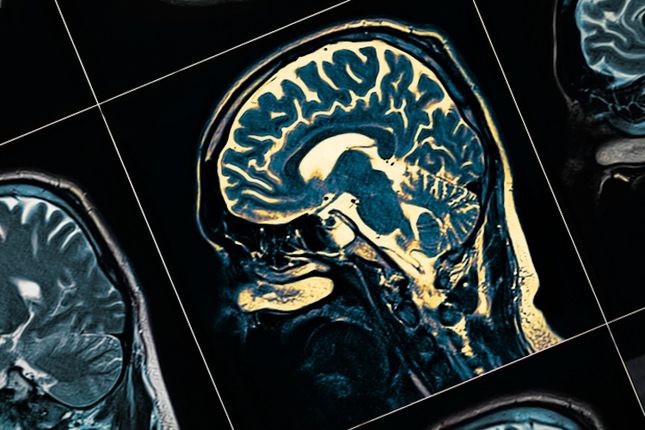

The report shows dementia remains the leading cause of death for Australian women and the second leading cause of death of all Australians.

Dementia Australia CEO Professor Tanya Buchanan said dementia is one of the most pressing health challenges facing Australia.

“With more than 421,000 people living with dementia in Australia, a figure that is expected to double in the next 30 years, dementia has a significant impact in our community and on our health services,” Prof Buchanan said.

“We know from Australian and international research that dementia is a poorly understood condition, yet it is one of the leading causes of death for Australians. Dementia is not a normal part of the ageing process. It is however, one of the major health challenges facing Australia.